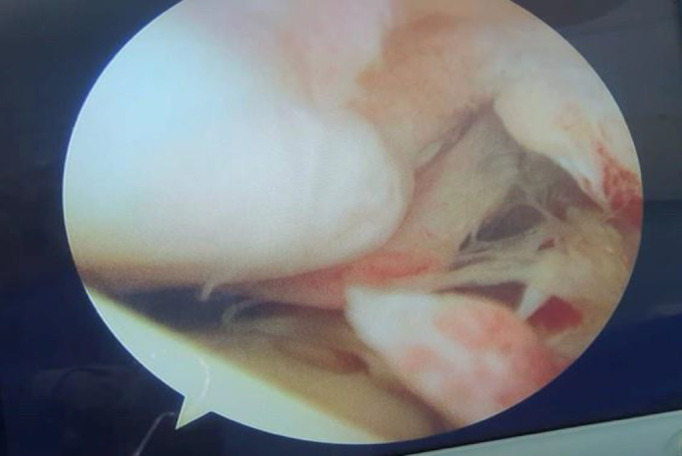

Abstract Image